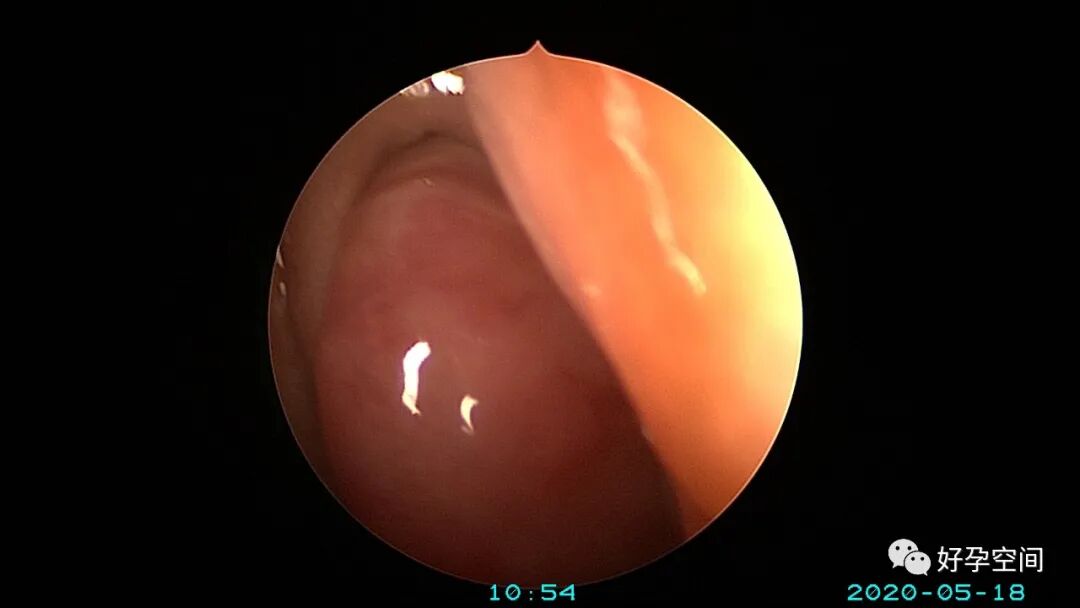

病例3:(病人年龄及取卵个数不详)取卵术后血尿膀胱内血块尿潴留,膀胱灌洗效果不佳,宫腔镜探查膀胱,清除血块,膀胱多处穿刺伤,电凝止血。

病例4:32岁,取卵13枚,取卵术后血尿膀胱内血块尿潴留,膀胱灌洗效果不佳,宫腔镜探查膀胱,清除血块,膀胱底见穿刺伤,电凝止血。